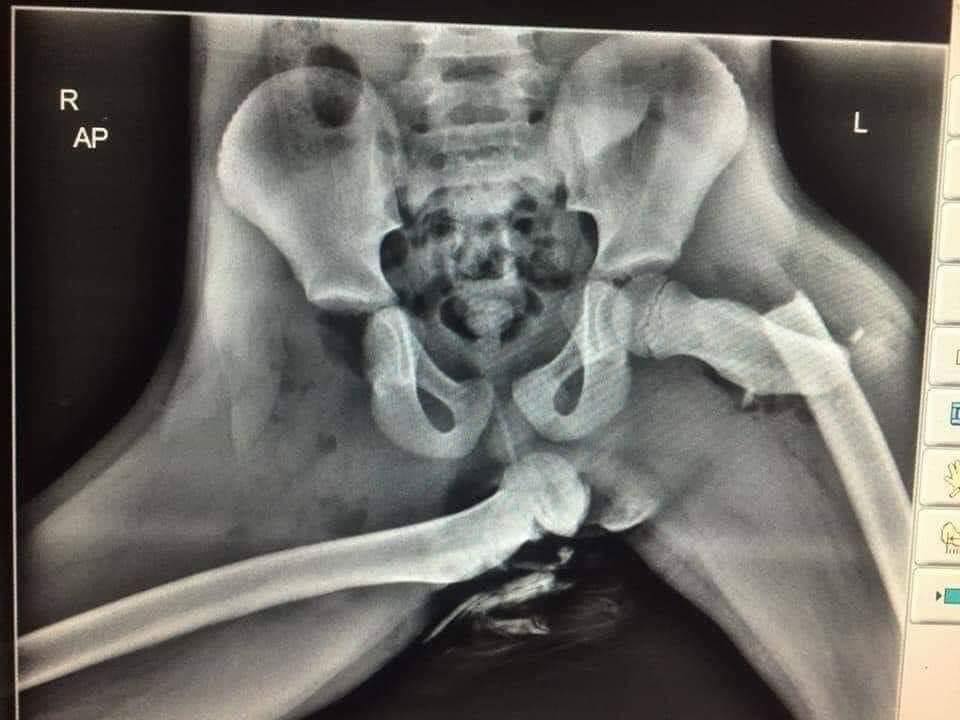

"Für diejenigen unter euch, die gerne als Beifahrer in einem Auto die Füße auf das Armaturenbrett legen. Das passiert, wenn der Airbag auslöst"

Facebook / Freiwillige Feuerwehr Premnitz